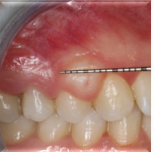

口内检查发现患者13、14牙间牙龈肿胀,质硬,无蒂,牙龈周围轻度菌斑堆积,牙龈轻度红肿。13、14牙不松动。

计划切除增生牙龈。由于增生范围较大,拟利用腭侧牙龈进行软组织修复。